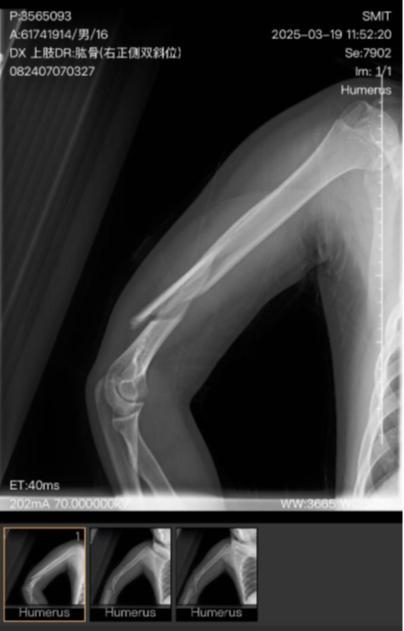

日前,记者接到河北秦皇岛的周先生反映,其子小明(化名)是秦皇岛市职业技术学校的高一学生,今年3月19日早上8时20分左右,小明因前一晚在宿舍说话被罚站,最终被教工扔起摔伤,造成右胳膊粉碎性骨折,右桡神经损伤。

秦皇岛市第一医院一份手术记录显示,3月21日,小明因右肱骨粉碎性骨折、右桡神经损伤进行手术治疗。